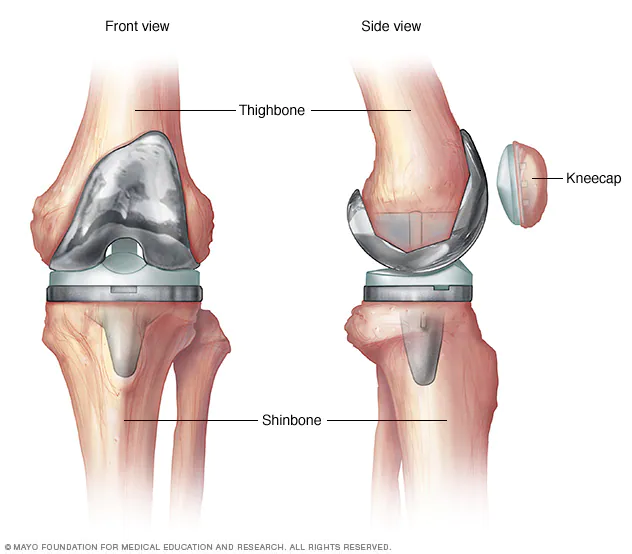

Knee replacement surgery — also known as knee arthroplasty — can help relieve pain and restore function in severely diseased knee joints. The procedure involves cutting away damaged bone and cartilage from your thighbone, shinbone and kneecap and replacing it with an artificial joint (prosthesis) made of metal alloys, high-grade plastics and polymers.

A total knee replacement is a surgical procedure whereby the diseased knee joint is replaced with artificial material. The knee is a hinge joint that provides motion at the point where the thigh meets the lower leg. The thighbone (or femur) abuts the large bone of the lower leg (tibia) at the knee joint. During a total knee replacement, the end of the femur bone is removed and replaced with a metal shell. The end of the lower leg bone (tibia) is also removed and replaced with a channelled plastic piece with a metal stem. Depending on the condition of the kneecap portion of the knee joint, a plastic "button" may also be added under the kneecap surface. The artificial components of a total knee replacement are referred to as the prosthesis.

The posterior cruciate ligament is a tissue that normally stabilizes each side of the knee joint so that the lower leg cannot slide backward in relation to the thighbone. In total knee replacement surgery, this ligament is either retained, sacrificed, or substituted by a polyethylene post. Each of these various designs of total knee replacement has its own particular benefits and risks.

A partial knee replacement surgery in International standards to replace only one part of a damaged knee. It can replace either the inside (medial) part, the outside (lateral) part, or the kneecap part of the knee. Surgery to replace the whole knee joint is called total knee replacement.

Partial knee replacement surgery removes damaged tissue and bone in the knee joint. It is done when arthritis is present in only part of the knee. The areas are replaced with a man-made implant, called a prosthetic. The rest of your knee is preserved. Partial knee replacements are most often done with smaller incisions, so there is less recovery time.